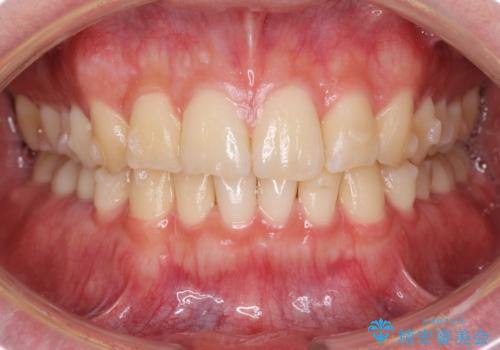

前歯のがたつきをなおしたい マウスピース矯正

- 気になる前歯のがたつきをきれいにしたい。と矯正治療を希望され来院されました。

大きな歯列の乱れはないため、倒れ込んでいる奥歯の傾きの改善、前歯のがたつきを改善する治療を計画します。

見た目が良くなっただけではなく、歯ブラシがしやすくなった!と治療後の歯並びに喜んでいただくことができました。